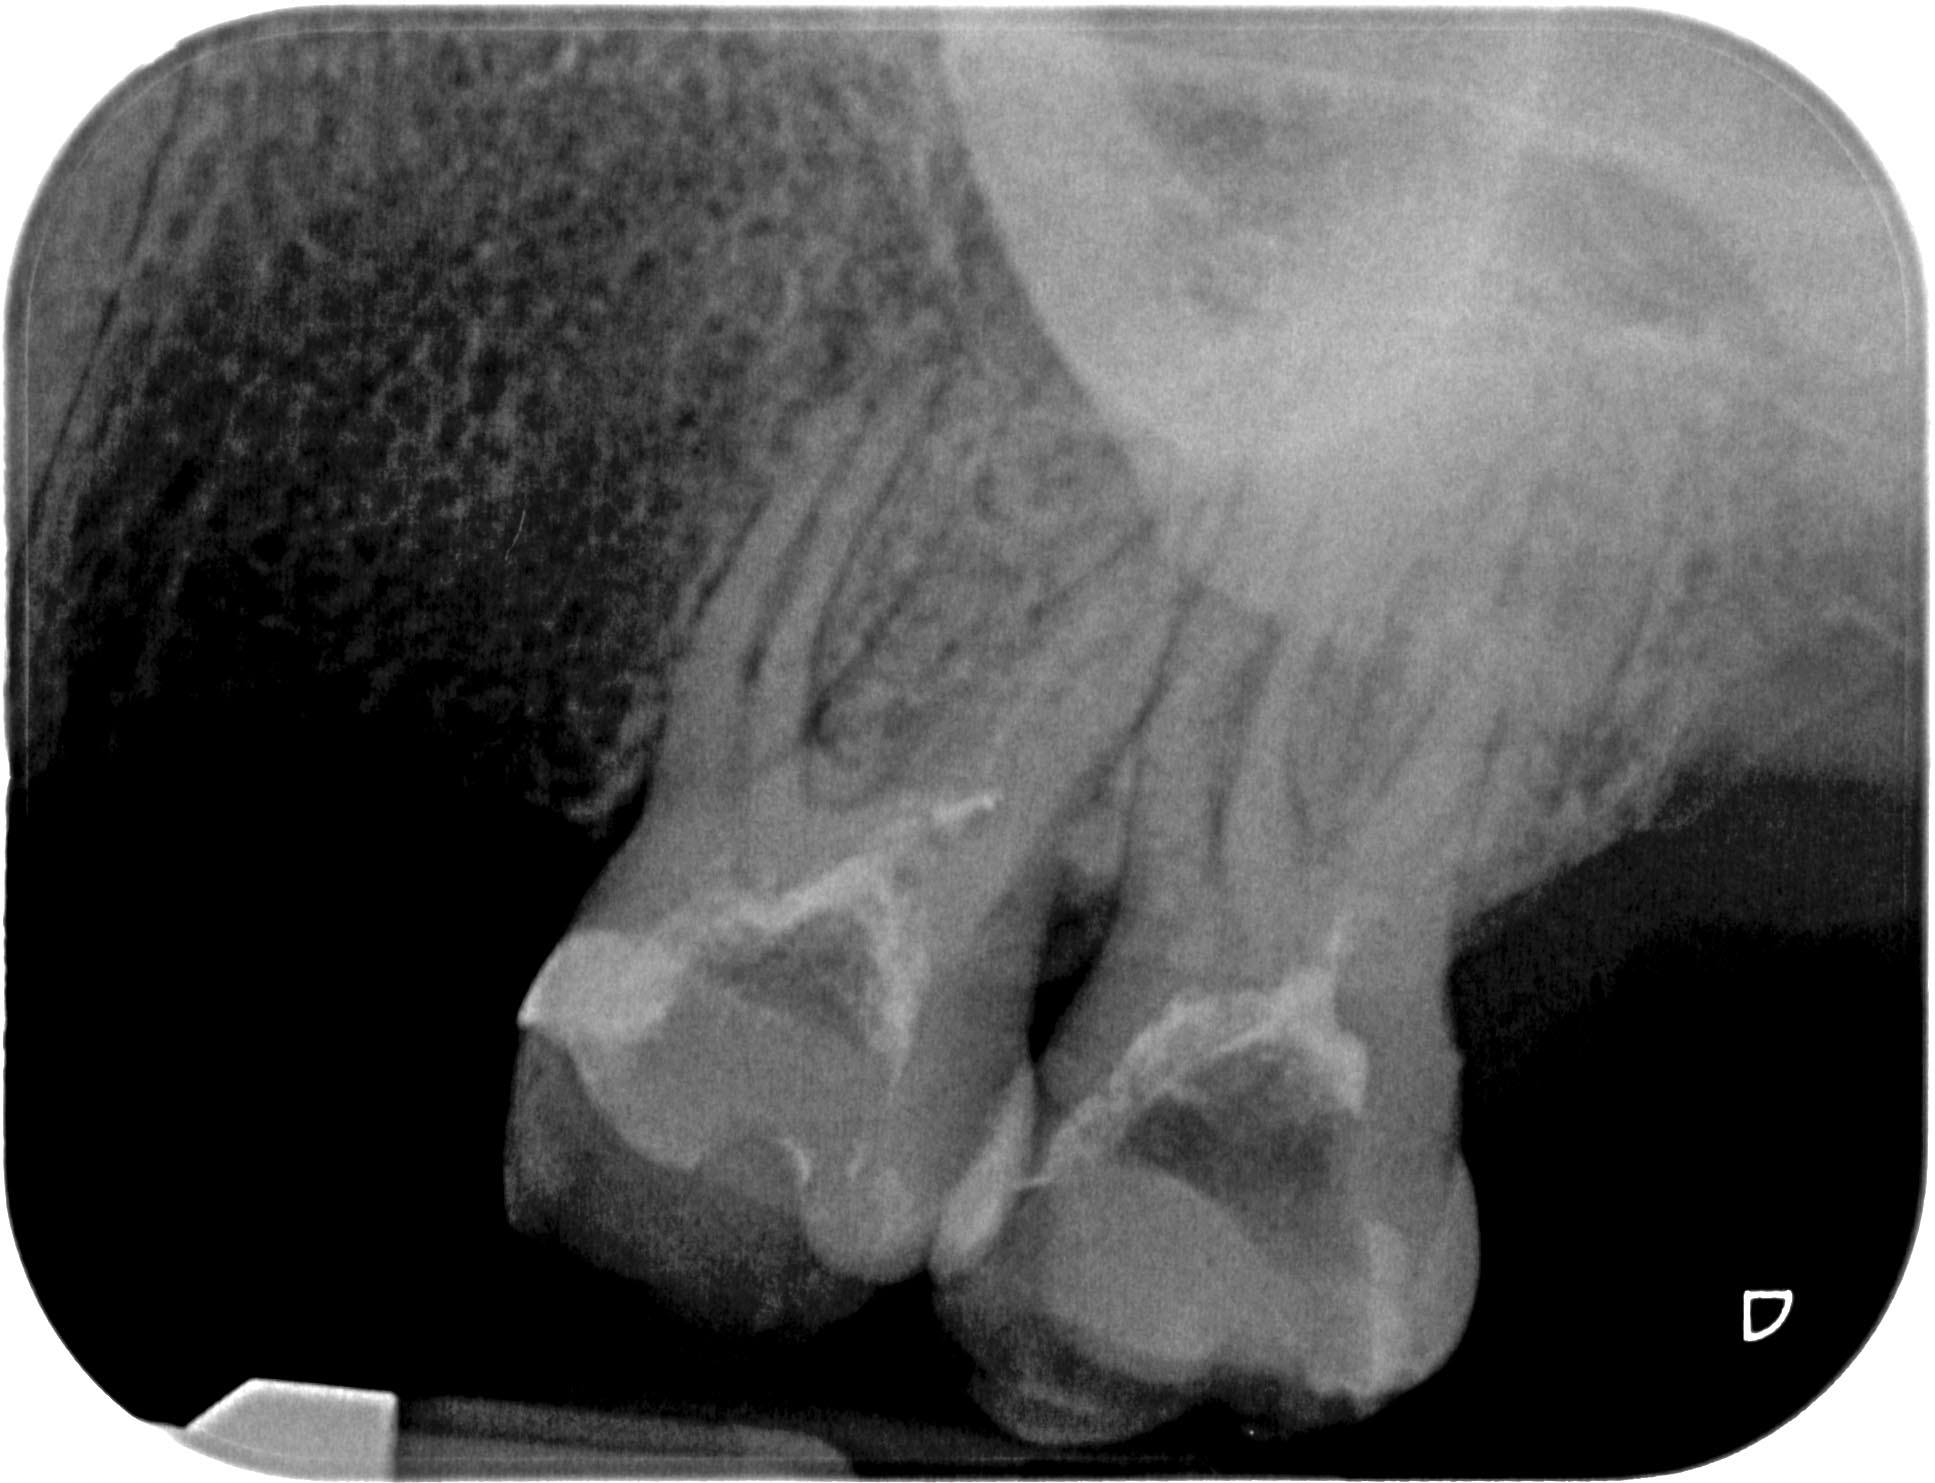

BN2627_1a-15 Veröffentlicht 1. Dezember 2014 am 1935 × 1483 in Unerwartete Anatomie Zahn 26, 27- die WF